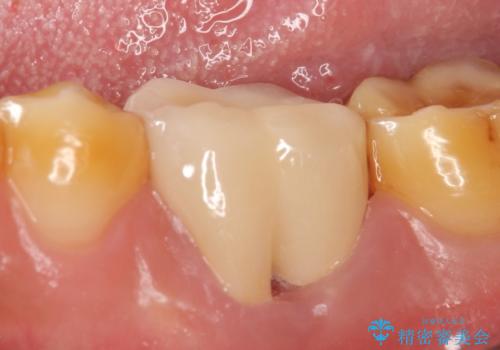

金属の縁が見えてしまったクラウン オールセラミッククラウンで審美的に